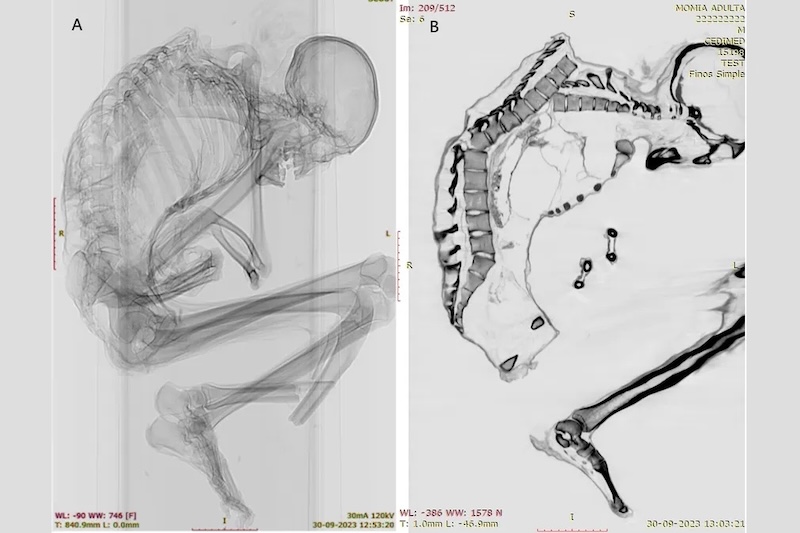

International Journal of Osteoarchaeology dergisinde yayımlanan çalışmada, Şili’nin Santiago kentindeki Ulusal Doğa Tarihi Müzesi’nde görev yapan arkeologlar Catalina Morales ve Francisco Garrido, erkeğin ölümüne yol açmış olması muhtemel ağır travmanın ayrıntılarını ortaya çıkarmak için BT taramaları ve röntgen görüntülemeleri kullandı.

Erkeğin üst omurgasında iyileşmemiş çok sayıda kırık tespit edildi. Ayrıca kaburga, kürek kemiği ve köprücük kemiği kırıkları da vardı. Bunlar, araştırmacıların çalışmada yazdığına göre, sırtın üst kısmında “geniş bir alana yayılan künt kuvvetli bir darbeyi” düşündürüyor ve “üst sol göğüs kafesinin darbenin asıl yükünü taşıdığını” ortaya koyuyordu. Darbe, omurların bir kısmını yerinden oynatmış ve göğüs kafesinin çökmesine neden olmuştu.

Bunun yanı sıra, omurganın tabanına yakın bir omurda da kırık belirlendi; bu kırık muhtemelen üst sırt yaralanmasının dolaylı sonucu olarak oluşmuştu. Araştırmacılar, üst ve alt omurga yaralanmalarının her ikisinin de “genellikle ağır omurilik hasarı ve yüksek ölüm oranıyla ilişkili” olduğunu söylüyor.

Buna karşın, erkeğin kafatasında, boynunda ya da kollarında herhangi bir yaralanma saptanmadı. Bu durum, darbenin erkeğin baş aşağı bir vücut pozisyonundayken gerçekleştiğine işaret ediyor. Kişi ya aktif biçimde kazı yapıyordu ya da yukarıdan düşen ağır bir nesne çarptığında kollarıyla başını korumaya çalışıyordu. Araştırmacılara göre bu tür yaralanmalar, depremde yaralanan insanların bedenlerinde ve ormancılık, inşaat ve madencilik gibi mesleki kazalarda görülebiliyor.

Araştırmacılar çalışmada, “Arkeolojik bağlam göz önüne alındığında, bu birey muhtemelen turkuaz çıkarırken, maden tavanından sırtına düşen bir kaya nedeniyle öldü, fakat antik madencilerin yaşam koşullarını daha iyi anlayabilmek için daha fazla araştırmaya ihtiyaç var” diyor.